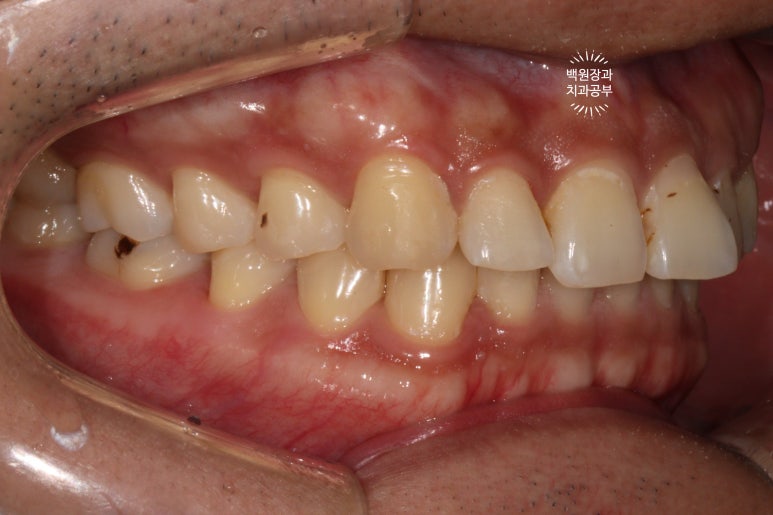

고개를 돌려서 우측을 보시면, 까맣 까맣하게 보이는 부위들이 있는데 대부분이 '레진 변색' 입니다.

레진 변색은 끝부분만 잘 다듬어드리면, 굳이 기존의 레진을 제거하고 다시 치료할 필요가 없어요!!!

-> 이게 포인트~!! 다시 뜯고 떼우는 것은 과잉진료입니다.